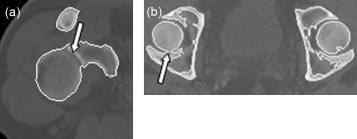

Como ejemplos, observamos que en la figura 7 a la articulación del hombro derecho se detecta de manera incorrecta, identificándose el húmero como parte de la escápula, y la figura 7 b muestra un corte perteneciente a la pelvis; en este caso, el fémur izquierdo se identifica como parte del hueso iliaco, cosa que no sucede con el lado derecho.

Casos donde falla el algoritmo de detección de contornos: a)articulación del ...

Casos donde falla el algoritmo de detección de contornos: a) articulación del hombro derecho, y b) articulación del fémur.